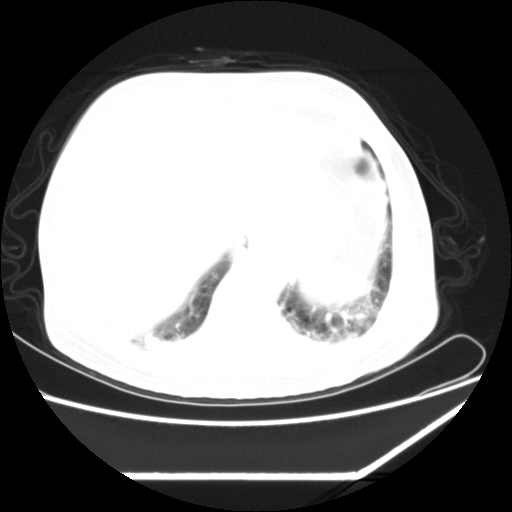

男,57,畏寒,发热

两肺野多发大小不一高密度灶,纵膈内见肿大淋巴结,要考虑转移瘤可能。双侧胸腔少量积液。

双肺多发结节样病灶,部分内见透光区,纵隔内见淋巴结肿大。结核临床如有畏寒,高热,白细胞增高首先考虑迁徙性肺脓肿(多是金黄色葡萄球菌感染)。

注意除外转移瘤。

1)考虑两肺感染性病变(金黄色葡萄球菌肺炎?);建议抗炎治疗后复查排除其他。2)双侧少量胸腔积液。